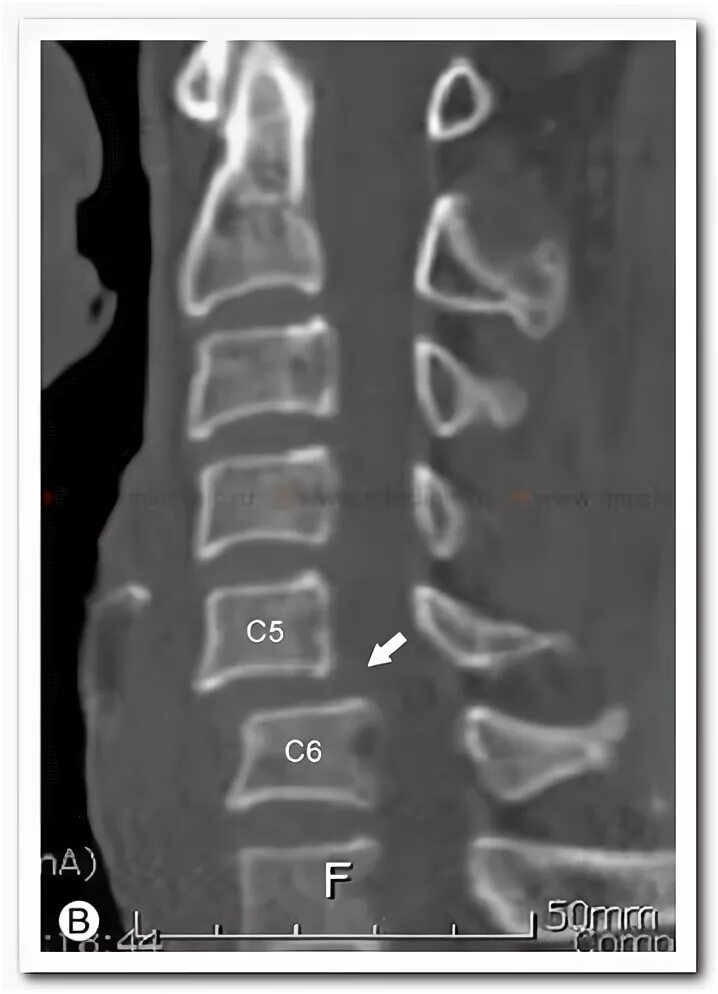

Нестабильность сегмента с3